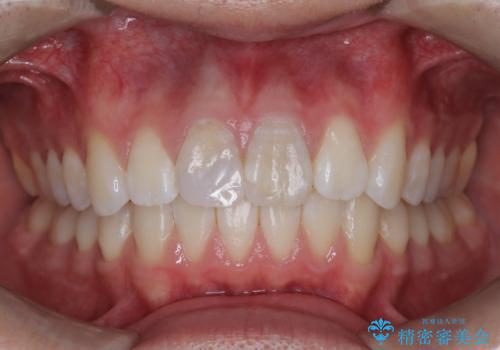

正面から見たときに右上2が全く見えないくらい、右上2が後ろに引っ込んでいる状態でしたが綺麗に並べる事が出来ました。

笑った時のスマイルラインもかなり綺麗になり大変ご満足いただく事が出来ました。

スムーズに治療を進める事ができ、2年2か月で治療をお終えました。

顔貌に対して歯の正中も合いました。